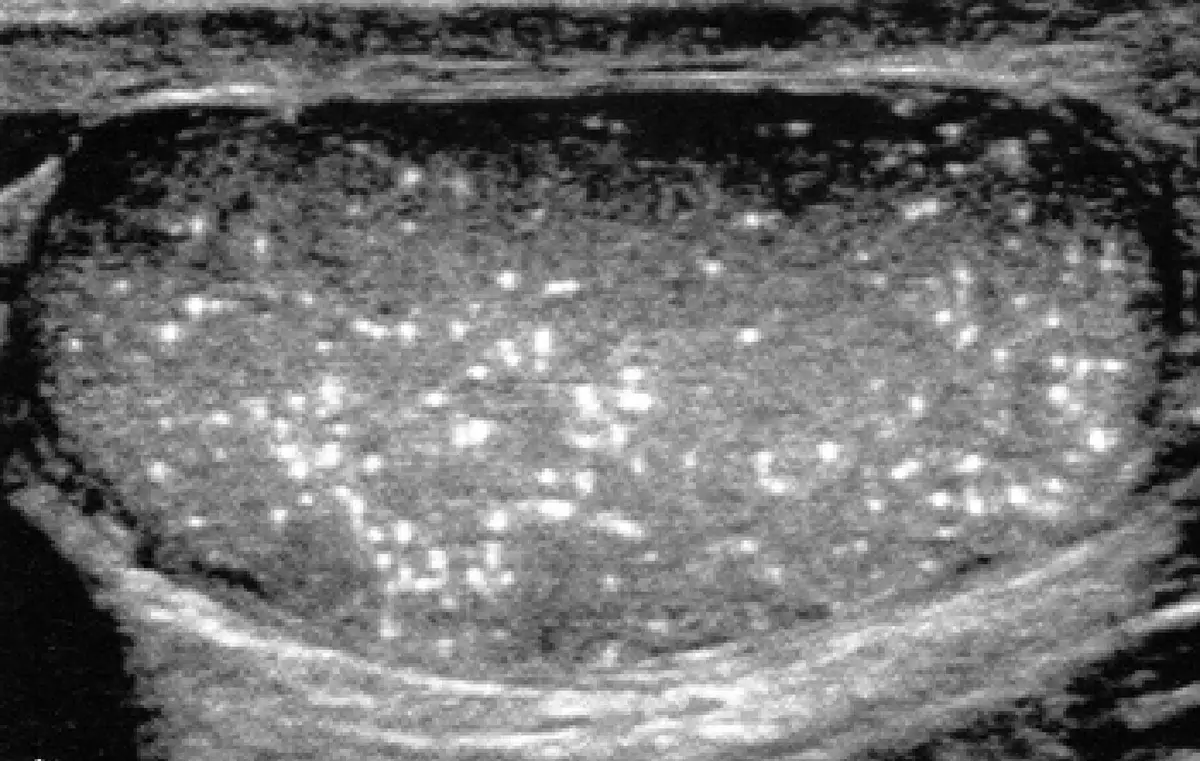

附圖為人類陰囊的超音波影像,最可能的診斷為下列何者?

本張超音波影像顯示整個睪丸實質內散布著大量細小、均勻的強回音(hyperechoic)亮點,數量眾多,密集分布於整個睪丸實質,形成如「暴雪(snowstorm)」般的影像特徵。這些亮點:

- 大小約 1–3 mm,均勻一致

- 不產生聲影(acoustic shadowing),此為與一般大結石鑑別的關鍵

- 廣泛散布於整個睪丸實質,而非局灶性

- 睪丸整體輪廓完整,無局部腫塊

此影像表現為睪丸微鈣化的經典「暴雪型」超音波模式,正確答案為微鈣化(A)。

(A) 微鈣化 ✅ — 正確。超音波顯示睪丸實質內彌漫性、無聲影的多發小強回音點,即微鈣化(microliths)的典型表現。每個鈣化點由退化的細胞碎片和鈣質沉積在精細管(seminiferous tubules)內形成。